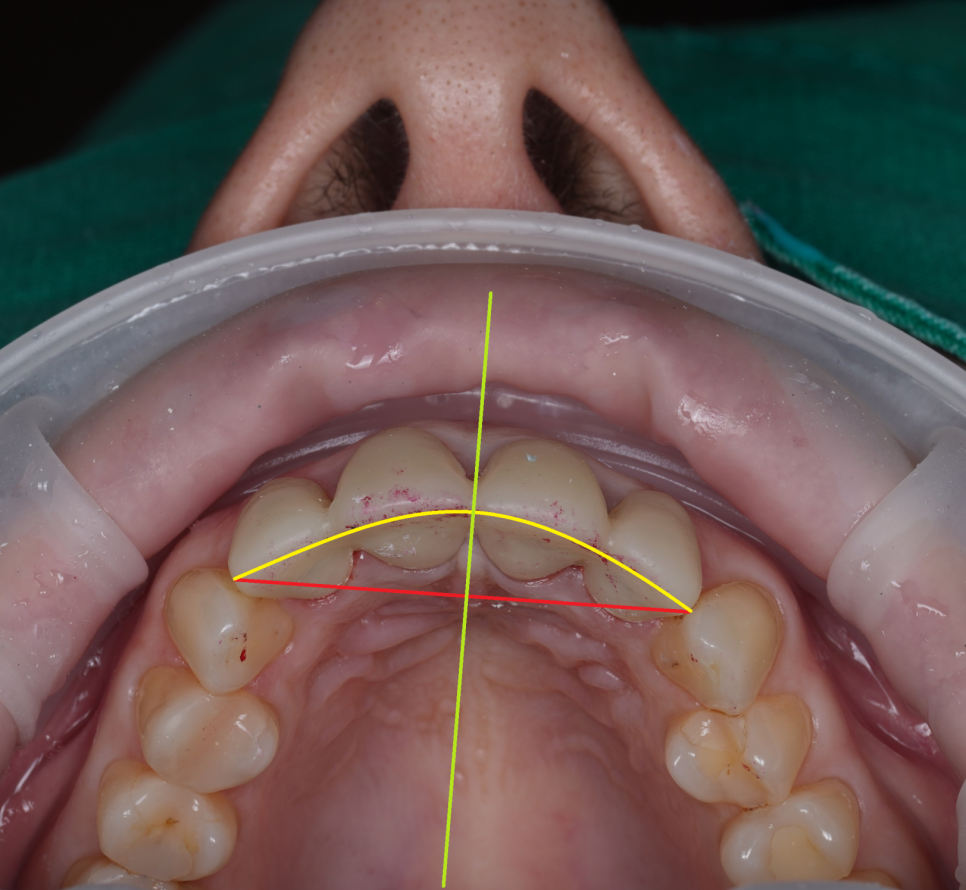

| 5) 얼굴과 치아 축의 틀어짐 |

이렇게 봤을 때 잘 모르실 수도 있는데요.

이렇게 선을 그어보면 틀어진 축을 볼 수 있습니다.